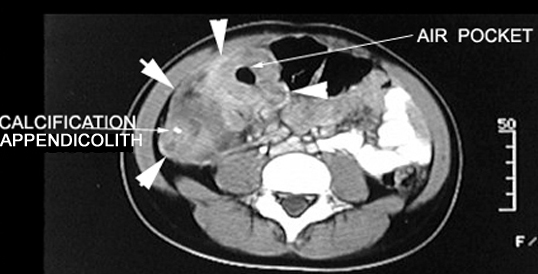

CT: Highly accurate

Signs: